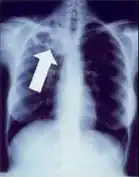

2. Any cavitary lesion - Lucency (darkened area) within the lung parenchyma, with or without irregular margins that might be surrounded by an area of airspace consolidation or infiltrates, or by nodular or fibrotic (reticular) densities, or both. The walls surrounding the lucent area can be thick or thin. Calcification can exist around a cavity.

-

Chest X-ray of a person with advanced tuberculosis: Infection in both lungs is marked by white arrow-heads, and the formation of a cavity is marked by black arrows.